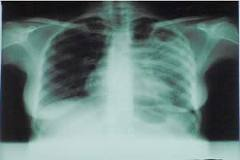

A tuberculose é uma doença infecto-contagiosa causada por uma bactéria que afeta principalmente os pulmões, mas, também pode ocorrer em outros órgãos do corpo, como ossos, rins e meninges (membranas que envolvem o cérebro).  A transmissão é direta, de pessoa a pessoa. O doente expele, ao falar, espirrar ou tossir, pequenas gotas de saliva que contêm o agente infeccioso e podem ser aspiradas por outro indivíduo contaminando-o. (Com informações da Ascom PMSMBV)